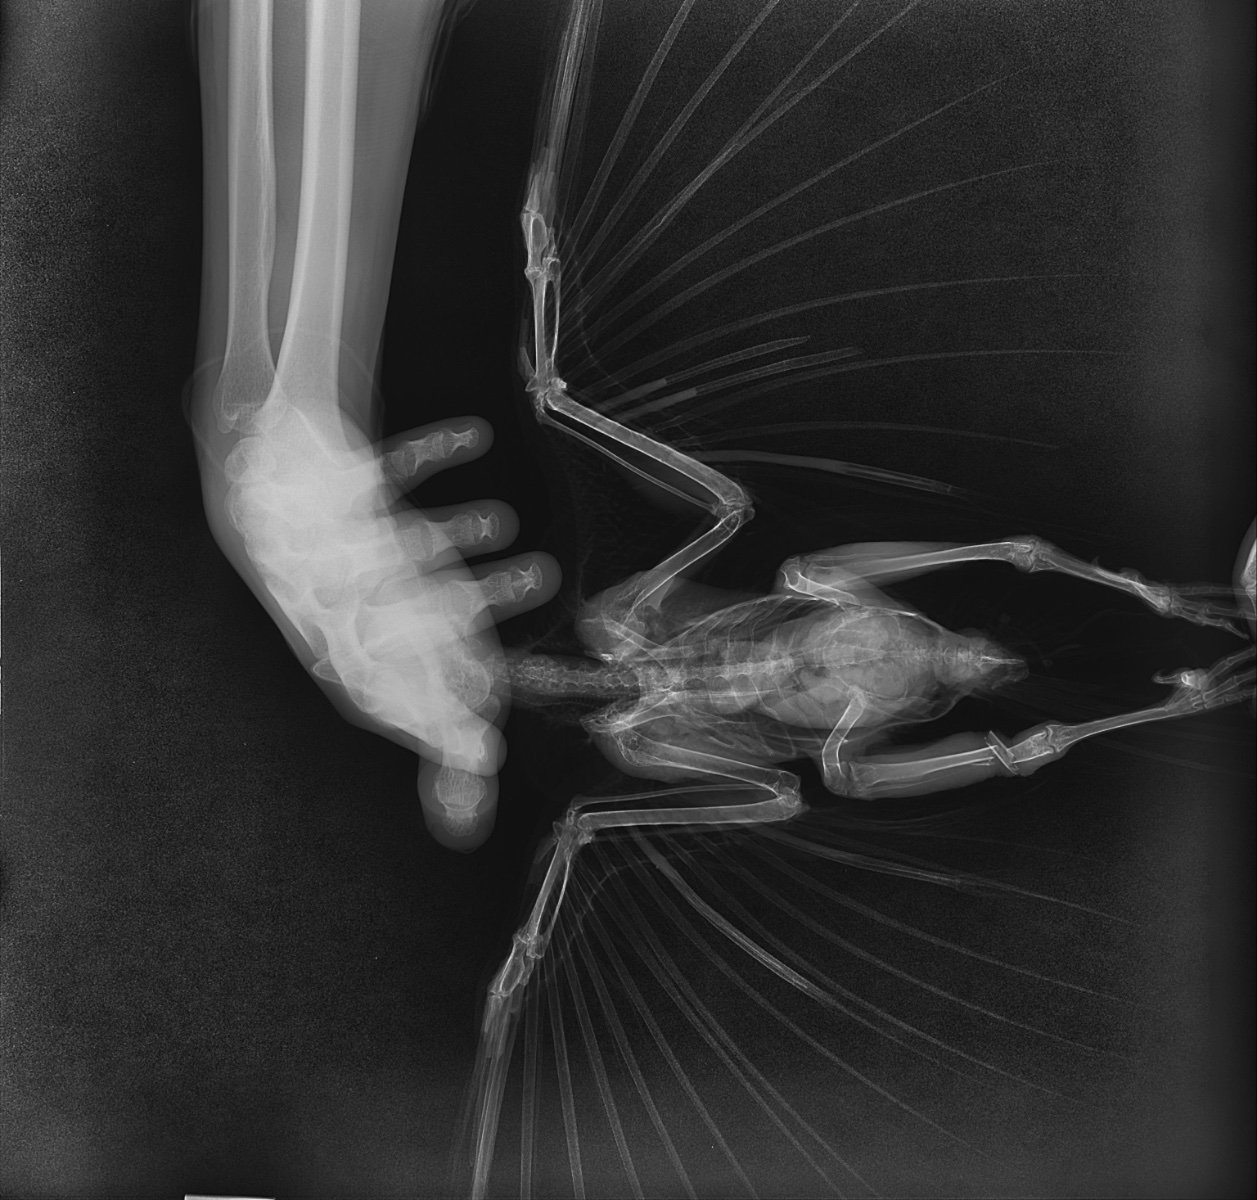

20240905005_Дегтянникова_Ворона_20240905162112.jpeg

20240905005_Дегтянникова_Ворона_20240905162124.jpeg

20240905005_Дегтянникова_Ворона_20240905162136.jpeg

У меня остаются подозрения, что где-то есть открытая рана, личинки не могут быть просто так. По рентгену не вижу, где могла бы быть. Лучше обратиться к Zosia, чтобы посмотрела рентген, быстрее будет по Вацапу в ее профиле.